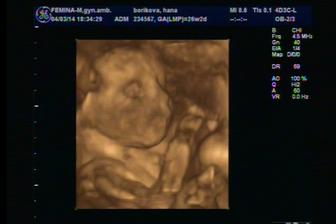

Termín pôrodu máme 8.jún 2014, už aby to bolo 🙂)

@evkasto áno už sa aj mrvíme, podľa Dr. máme aktívne bábo, aj jeho koplo keď nám robil sono 😀